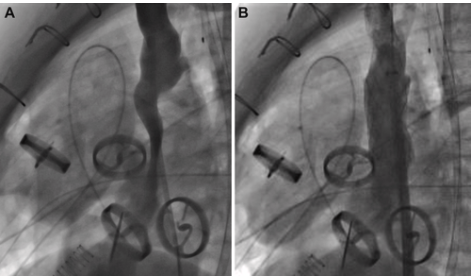

New Case Report in JACC A case from Jahanshad et al. at Morgan Stanley Children’s Hospital highlights the SynCardia TAH as a bridge to transplant in a 15-year-old with end-stage heart failure. See jacc.org/doi/abs/10.101… for the complete case report. #SynCardia

New Case Report in JACC

A case from Jahanshad et al. at Morgan Stanley Children’s Hospital highlights the SynCardia TAH as a bridge to transplant in a 15-year-old with end-stage heart failure.

See jacc.org/doi/abs/10.101… for the complete case report.